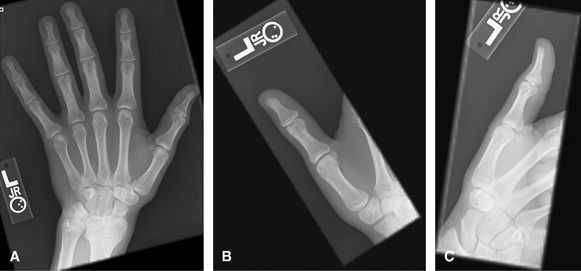

For 2nd–5th digits. Specifically to look at 1 finger for

trauma, foreign body, or localized mass. A marker should be applied,

particularly on the lateral projection. Consider US for radiolucent

foreign body. Consider MRI or US for mass or tendon lesion/injury.

![]() |

Figure 1 (A) PA hand. (B) Oblique of fingers. (C, D) Lateral of fingers.